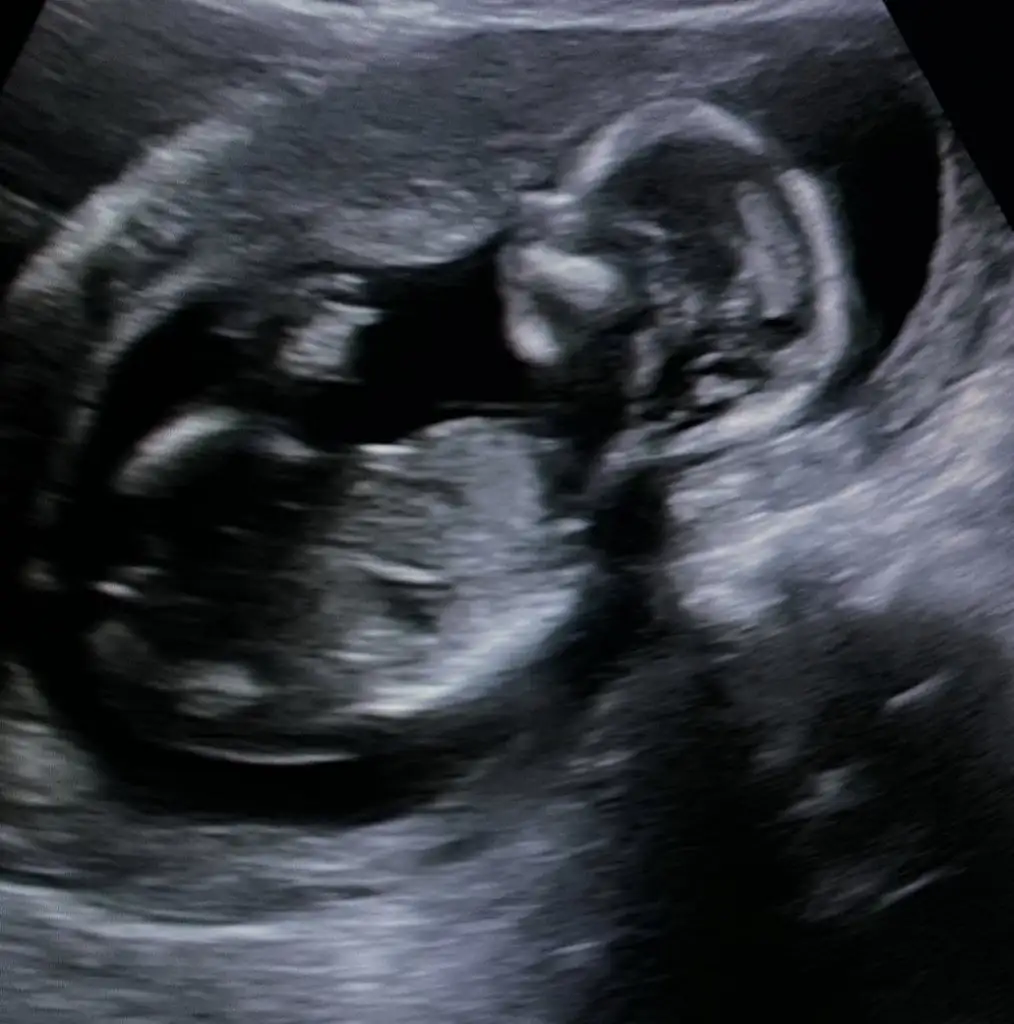

Ikra meyra daha küçük 8 haftalık ama tahminde bulanabilir misiniz

Eklentiler

• image.webp

34 KB · Görüntüleme: 53

26,7 KB · Görüntüleme: 48

14,5 KB · Görüntüleme: 49

30,3 KB · Görüntüleme: 64

Hepinize cinsiyet tahmini yapmak isterdim ama bazen ultrasondan anlamıyorum bazen de pozisyonu uygun olmuyo.mesela 3numara sizin bebişiniz bacaklarını kaldırmış arada görülen pipi mi nub çıkıntısı mı onu anlamadım konuya çok geç dahil oldum biraz daha ihtisas yapmam lazım